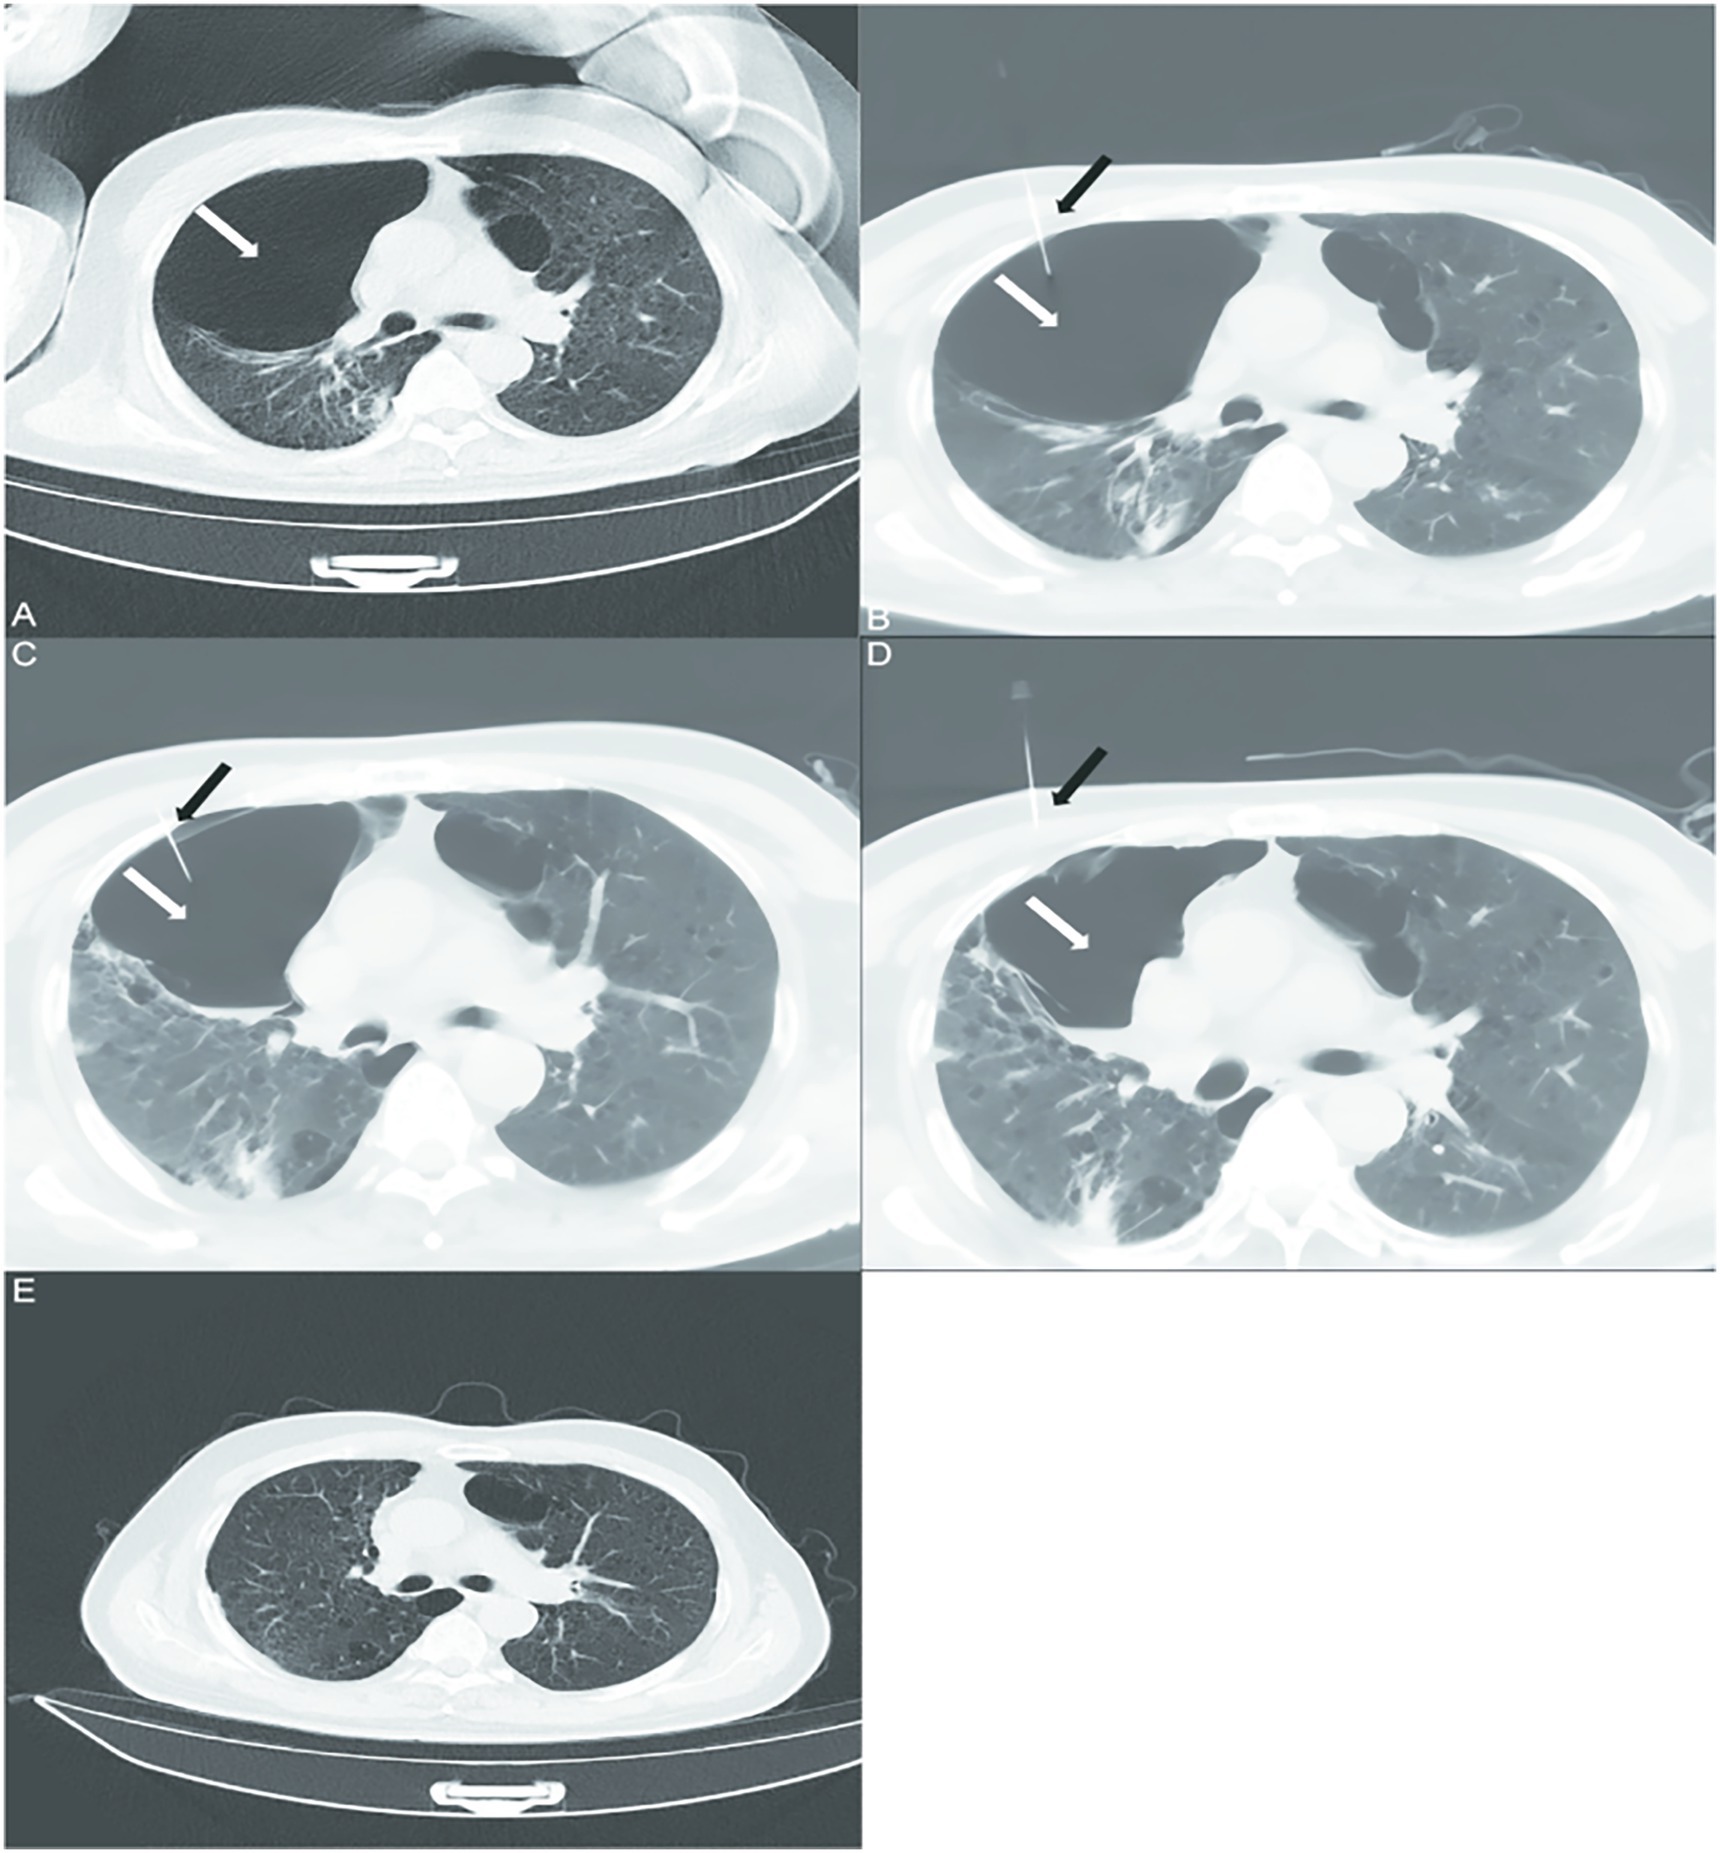

A 70-year-old man with severe COPD (GOLD stage 3, FEV1 < 48% predicted) and a past medical history significant for hypertension and coronary artery disease status post percutaneous coronary intervention 5 years prior, and 40-pack-year smoking history presented to hospital with recurrent cough, productive sputum, and progressive dyspnea worsening over 12 months despite maximal medical therapy (long-acting muscarinic antagonist/long-acting agonist, inhaled corticosteroids, home oxygen at 2 L/min). Physical examination findings were consistent with severe COPD and the presence of large bullae. There was no significant family history of genetic lung disease (e.g., alpha-1 antitrypsin deficiency) or other relevant psychosocial factors beyond the reported smoking history. Baseline high-resolution computed tomography (HRCT) revealed bilateral giant emphysematous bullae with the dominant lesion measuring 8.5 cm× 6.2 cm in the right upper lobe, compressing adjacent parenchyma (Figure 1A). Following multidisciplinary assessment, the patient—deemed high-risk for surgery due to severe air trapping and chronic hypercapnia—underwent a novel percutaneous aspiration and sclerotherapy for staged reduction of pulmonary bullae (PASS) protocol (Table 1) on the first day, under local anesthesia and CT guidance (Philips, Precedence 16, Netherlands), a puncture needle was directly inserted into the patient’s lung cavity, and polidocanol was injected into the cavity to ensure adequate contact with the pulmonary bullae (Figure 1B). The patient was rotated through prone, supine, and lateral decubitus positions to maximize sclerosing agent contact with bulla walls. On the second day, when the puncture needle was inserted again, an attempt was made to aspirate gas, but it proved challenging, and no reduction in the size of the bullae was observed. The injection of polidocanol into the cavity continued (Figure 1C). On the third day, gas aspiration was successful after inserting the puncture needle into the lung cavity, and polidocanol injection continued (Figure 1D). Peri-procedural monitoring showed stable oxygen saturation (SpO2 92–95% on 2 L/min nasal cannula) without pneumothorax or hemodynamic compromise. Post-procedure chest radiographs confirmed the absence of iatrogenic complications. At 3-month follow-up, HRCT demonstrated >70% volume reduction of the dominant bulla (residual size 2.8 cm× 3.1 cm) with re-expansion of compressed lung tissue (Figure 1E), correlating with significant symptomatic improvement: mMRC dyspnea scale decreased from 4 to 2, 6-min walking distance increased from 182 m to 310 m, and chronic oxygen therapy was discontinued. Subjectively, the patient reported a marked improvement in his ability to perform activities of daily living independently and expressed high satisfaction with the procedural outcome.

Figure 1. Axial computed tomography scans of the chest in patients with bilateral emphysema and alveoli before and after treatment with percutaneous bullae reduction surgery. (A) Chest CT shows emphysema and pulmonary bullae in both lungs(white arrows). (B–D) A puncture needle (black arrows) was inserted into the patient’s lung cavity on 3 consecutive days, and the air was aspirated and injected with polidocanol. (E) On follow-up chest CT at 3 months of treatment, the patient’s pulmonary alveoli showed significant improvement.